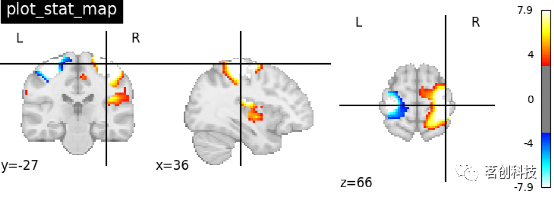

plot_stat_map:绘制统计图像,如T图、Z图或ICA。

from nilearn import plotting

# 在EPI模板上手动可视化t-map图像

# 使用给定的cut_coords定位坐标

plotting.plot_stat_map(stat_img,

threshold=3, title="plot_stat_map",

cut_coords=[36, -27, 66])